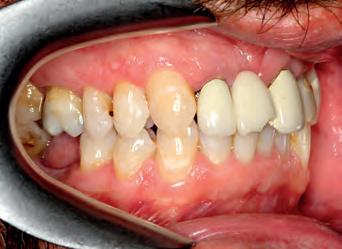

Patient: face before

A53 year old man attended complaining of pain from an existing bridge UR2 - UL2. It needed to be extracted because several roots were infected and would have required re-RCT, which the patient did not want to do. On closer inspection, the remaining teeth in the upper arch required some work as well (one RCT), but otherwise the teeth had a good prognosis.

The options were explained to the patient (implants, bridges/crowns/dentures) and the patient decided to save his remaining teeth. Written and verbal consent was obtained. We took clinical records and a series of DSLR photos and intraoral scanning with the Carestream 3600 intra oral scanner with scan flow software. The CS 3600 was chosen because of the comprehensive restorative features such as checking how much tooth structure has been removed compared to the pre-op tooth shape, as well as checking for any undercuts.

The decision was made, to extract the remaining upper incisors and make a temporary bridge from UR3 - UL3 in Luxatemp A3 with no immediate change to tooth shape or smile design.

TOP ROW: Before lower occlusal, Before retracted in occlusion 2ND ROW: Before retracted left in occlusion, Before retracted left open 3RD ROW: Before retracted open, Before retracted right in occlusion 4TH ROW: Before retracted right open, Before upper occlusal